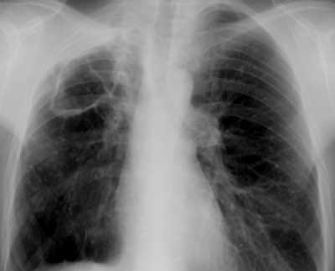

DESCRIERE:

pe tot teritoriul pulmonar, bilateral → multiple opacități micronodulare diseminate, de intensitate mare

la niv. hilului drept → opacitate policiclică (blocuri adenopatice)

DX: miliara TBC

DD:

miliara carcinomatoasă

bronhopneumonie

→ distribuție predominant bazală, noduli de dimensiuni mai mari, fără ADP